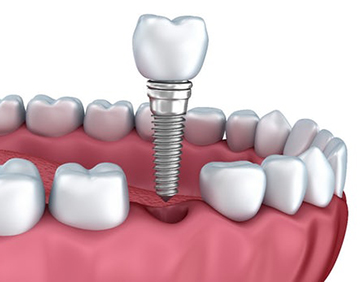

Імплантація зуба - це процедура, яка полягає у введенні в кістку пацієнта стороннього тіла. При цьому дуже важливо, щоб імплантат зуба не відкидався організмом, створюючи дискомфорт для пацієнта.

Щоб імплантування зубів пройшло успішно, його має проводити досвідчений лікар за допомогою високоякісних інструментів. Зубна імплантологія в нашій клініці – окремий напрямок діяльності, яким займаються виключно висококваліфіковані спеціалісти.